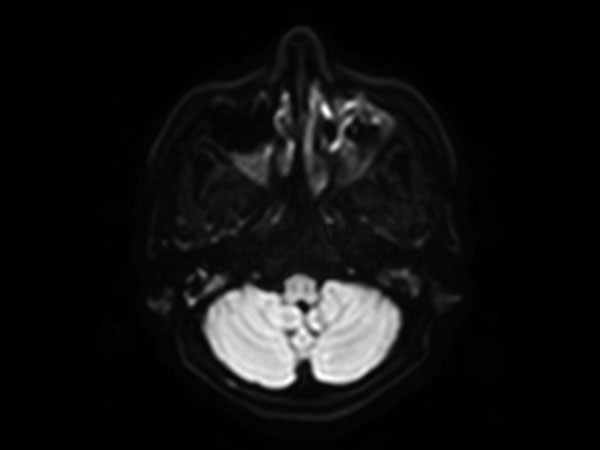

Axial mDIXON XD - T2w TSE (Water only)